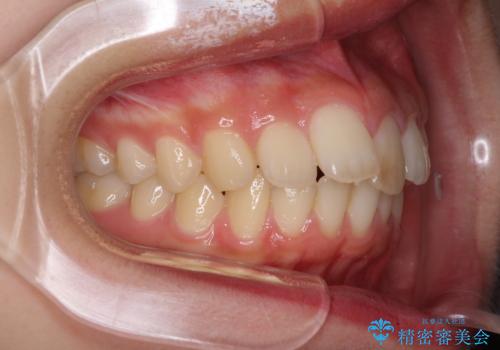

就職前にきれいな歯並びにしたい 大学生のインビザライン矯正

- 就職するまでに歯並びをきれいにしたいとのことで来院された患者様です。

前歯の叢生を気にしていましたが、極力突出感を改善できるようにすることとし、インビザラインにて矯正治療を行うこととしました。

改善の期待できない口元の突出感改善を希望されたため、いたずらに治療期間が延びましたが、きっちりと仕上がりました。